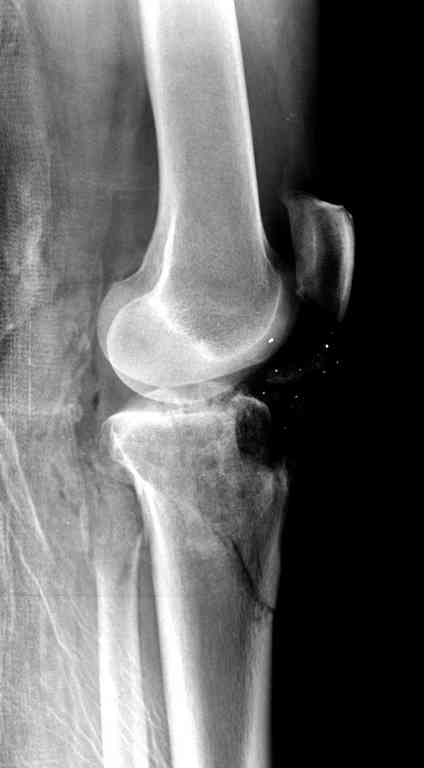

На вашем снимке из-за ротации трудно угадать положение пластины, и желательно сделать снимок с захватом верхнего участка бедра.

Одинокий кортикальный шуруп не удержит тибиальный бугор, сустав тибиал плато оставлен без репозиции и фиксации.

План с протезированием чересчур агрессивный, больная слишком молодая. В данный момент для удержания конструкции необходимо установить наружный фиксатор между бедром и голенью. Обработку продолжать с применением антибиотиков и вакуумирования.